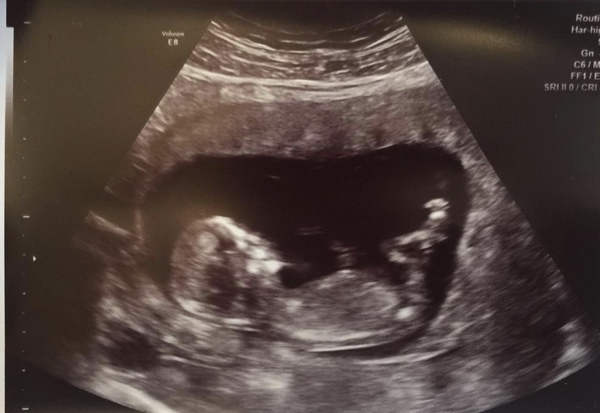

What do you think of this for skull theory? I’m finding out on Friday!

I'm having a girl- I've attached my latest scan for you to compare😊

Here’s mine

This was my 12 week photo.. and (although we're not really sharing, it's ok to on here) we are having a boy too!